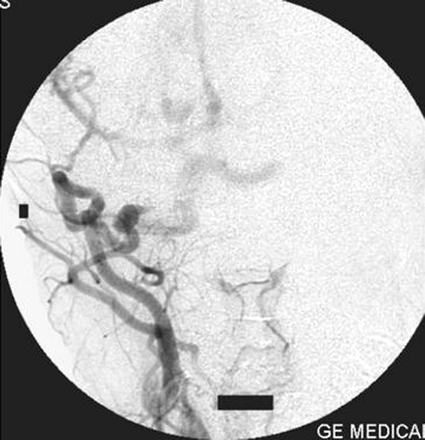

On the right external carotid artery angiogram, the carotid-basilar anastomotic vessel was seen to arise from the external carotid artery at the second cervical vertebral body (C2) level. The vessel coursed dorsally and joined the vertebral artery in the suboccipital space (Figs 6, 7). Contrast medium was seen to opacify the fistulous site and was draining via the left transverse sinus.

Right external carotid artery injection lateral view angiogram shows the proatlantal artery.

Right external artery injection anteroposterior view angiogram shows the opacification of the proatlantal artery of the right side.